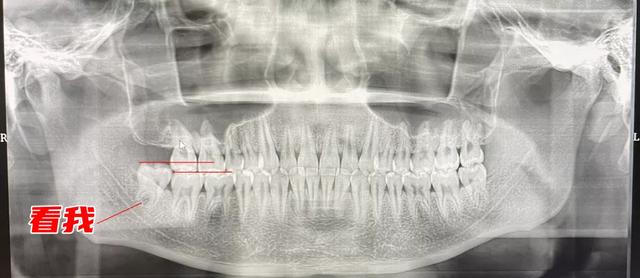

什么是“对颌伸长”呢?可以看一看我的牙片,左下角那颗就是被拔除的。我画了两条线,大家可以看到,这颗牙的水平线和其他牙有着明显的高度差。

图片来源:格格拍的

这是因为,去年在它上面的那颗智齿被拔除了,它上面没有了“天花板”,就开始放飞自我,肆意生长,这就是对颌伸长。